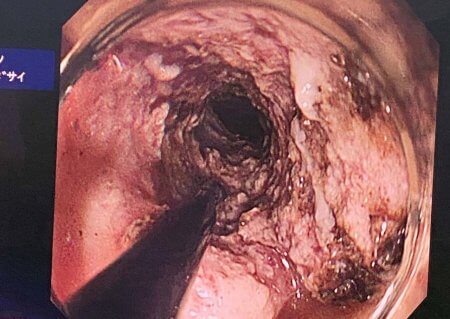

Anamnezidan ma’lum bo‘lishicha, bemor qizilo‘ngachning o‘rta uchligi o‘sma kasalligi bilan bir necha marta davolangan. So‘nggi yillarda turli tibbiyot muassasalarida muntazam davolanganiga qaramay, ijobiy natija kuzatilmagan. Filial mutaxassislari tomonidan bemor to‘liq tekshiruvdan o‘tkazilib, unga “qizilo‘ngach o‘rta uchligi o‘smasi, qizilo‘ngach bo‘shlig‘iga o‘sishi bilan asoratlangan, qon ketishi (FIB)” tashxisi qo‘yildi.

Bemorda respublikada ilk bor mustaqil ravishda “ELSA” endoskopistlar assosiatsiyasi a’zosi, filial bosh endoskopisti A. Haydarov, Z. Bafoyev, U. Abidov, U. Ro‘ziyevlar tomonidan qizilo‘ngach o‘smasini shilliq va shilliq osti disseksiya qilish bo‘yicha kam invaziv murakkab endoskopik amaliyot bajarildi.

Operatsiya jarayoni xorijiy hamkor endoskopist mutaxassislar tomonidan telemedisina orqali kuzatib borildi. Jarrohlik amaliyoti muvaffaqiyatli o‘tkazildi va bemorning hozirgi ahvoli ijobiy bo‘lib, me’yoriy ovqatlanish va me’da-ichak tizimi faoliyati tiklanmoqda.